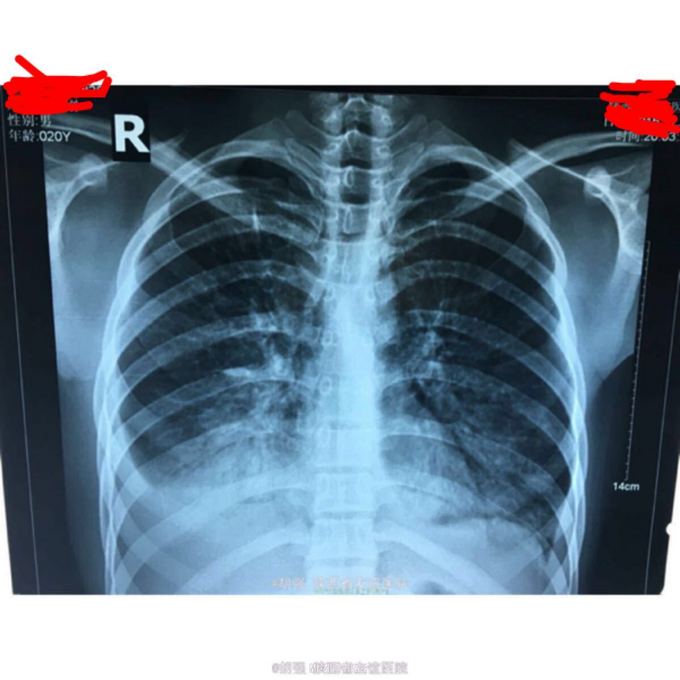

查体:口唇无发绀,咽充血,双侧扁桃体2度大,表面可见脓胎。两肺呼吸音粗糙,可闻及管状呼吸音。余查体无明显异常。 辅助检查:血常规提示白细胞及血小板明显低于正常值,肝功提示转氨酶升高。凝血系列:PT、APTT时间明显延长。T sport试验弱阳性。10月份胸部CT平扫未见明显异常。10月26日及12月12日胸片未见明显异常。12月19日胸部CT提示:两肺斑片状阴影,两侧胸腔积液。